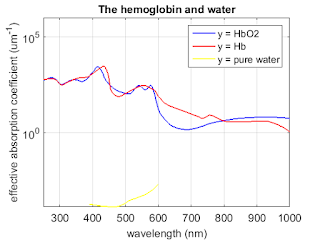

Matlab code to compute the corresponding absorption coefficients

% Matlab code to compute the corresponding absorption coefficients and plot

% the three absorption spectra on the same graph.

% Identify the low-absorption near-IR window that provide deep

% penetration.

% data for molar extinction coefficients of oxy-and deoxyhemoglobin and

% absorption coefficient of pure water as a function of wavelength are

% copied directly from this website: http://omlc.org/spectra/hemoglobin/summary.html

% Use physiologically representative values for both oxygen saturation SO2

% and total concentration of hemoglobin CHb.

% These values for the molar extinction coefficient e in [cm-1/(moles/liter)] were compiled by Scott Prahl using data from

%W. B. Gratzer, Med. Res. Council Labs, Holly Hill, London

%N. Kollias, Wellman Laboratories, Harvard Medical School, Boston

%To convert this data to absorbance A, multiply by the molar concentration and the pathlength. For example, if x is the number of grams per liter and a 1 cm cuvette is being used, then the absorbance is given by

%(e) [(1/cm)/(moles/liter)] (x) [g/liter] (1) [cm]

%A = ---------------------------------------------------

% 64,500 [g/mole]

%using 64,500 as the gram molecular weight of hemoglobin.

%To convert this data to absorption coefficient in (cm-1), multiply by the molar concentration and 2.303,

% µa = (2.303) e (x g/liter)/(64,500 g Hb/mole)

%where x is the number of grams per liter. A typical value of x for whole blood is x=150 g Hb/liter.

%% Absorption

figure;

semilogy(oxy_deoxy(:,1), oxy_deoxy(:,2)*0.0054, 'b', 'linewidth',1.5);

hold on

semilogy(oxy_deoxy(:,1), oxy_deoxy(:,3)*0.0054, 'r', 'linewidth',1.5);

hold on

semilogy(water(:,1), water(:,2), 'y', 'linewidth',1.5);

title('The hemoglobin and water','FontSize',14);

set(gca,'FontSize',14);

ylabel('effective absorption coefficient (um^{-1})','fontsize',14);

xlabel('wavelength (nm)','fontsize',14);

axis([250 1000 0 1*10^6]);

set(gcf,'PaperUnits','inches','PaperPosition',[0 0 6 5]);

grid on;

legend('y = HbO2 ','y = Hb', 'y = pure water')